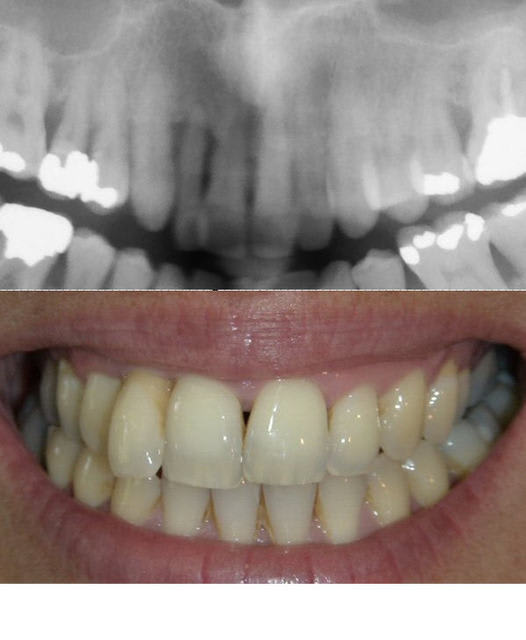

24/09/2007 à 05h32

simulation

sur Rx. du résultat du déplacement de 21/22/23/24 autour des apex

le résultat peut être amélioré en cas de béance,

courtoisement

Bjc.